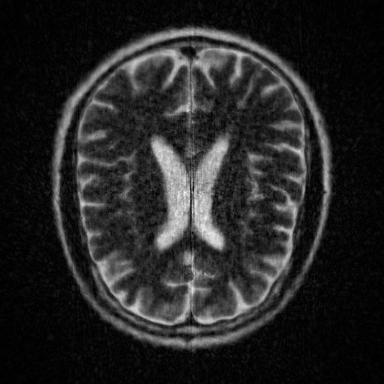

This article presents a novel undersampled magnetic resonance imaging (MRI) technique that leverages the concept of Neural Radiance Field (NeRF). With radial undersampling, the corresponding imaging problem can be reformulated into an image modeling task from sparse-view rendered data; therefore, a high dimensional MR image is obtainable from undersampled $k$-space data by taking advantage of implicit neural representation. A multi-layer perceptron, which is designed to output an image intensity from a spatial coordinate, learns the MR physics-driven rendering relation between given measurement data and desired image. Effective undersampling strategies for high-quality neural representation are investigated. The proposed method serves two benefits: (i) The learning is based fully on single undersampled $k$-space data, not a bunch of measured data and target image sets. It can be used potentially for diagnostic MR imaging, such as fetal MRI, where data acquisition is relatively rare or limited against diversity of clinical images while undersampled reconstruction is highly demanded. (ii) A reconstructed MR image is a scan-specific representation highly adaptive to the given $k$-space measurement. Numerous experiments validate the feasibility and capability of the proposed approach.